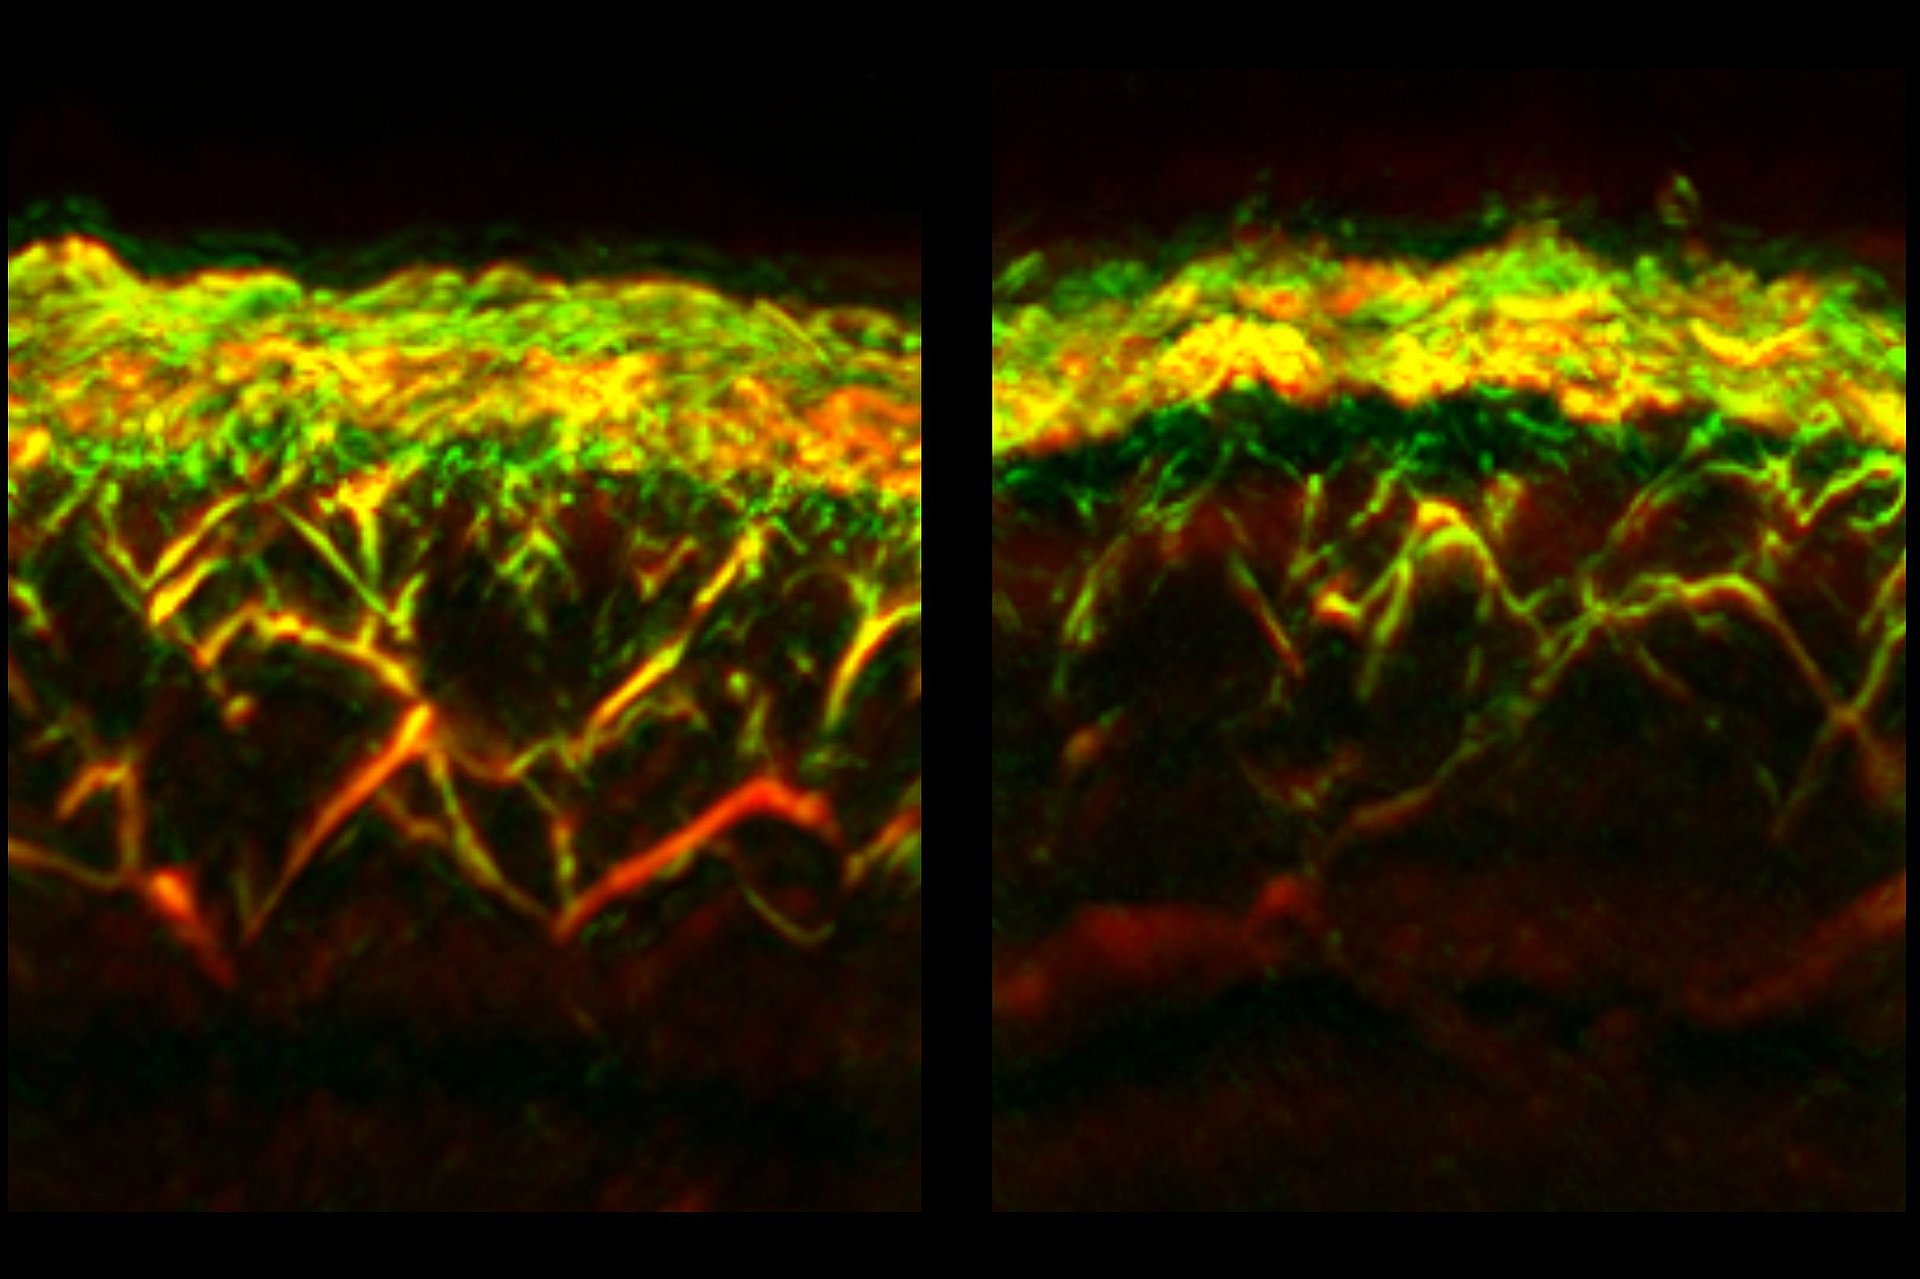

Optoakustische Bildgebungsmethoden verwenden Lichtimpulse, um Ultraschallwellen in Körpergewebe zu erzeugen. Diese Wellen werden von Sensoren erfasst und in Bilder umgewandelt. Erzeugt werden die Ultraschallwellen, wenn sich Körpergewebe um bestimmte Moleküle herum minimal zusammenzieht oder ausdehnt. Diese Moleküle, etwa Hämoglobin, absorbieren Licht besonders stark. Da Hämoglobin in Blutgefäßen konzentriert ist, lassen sich mit optoakustischer Bildgebung besonders detaillierte Bilder von Blutgefäßen erzeugen, die mit anderen nicht-invasiven Bildgebungsmethoden nicht möglich wären.

Jetzt hat das Team RSOM für die Untersuchung der Auswirkungen von Diabetes auf die menschliche Haut weiterentwickelt. Aus RSOM-Aufnahmen der Blutgefäße im Bein von 75 Diabetiker:innen und einer Kontrollgruppe identifizierten die Forschenden mit einem KI-Algorithmus Merkmale einer Diabetes-Erkrankung. Dabei erstellten sie eine Liste von 32 besonders aussagekräftigen Veränderungen im Erscheinungsbild der Äderchen der Haut. Dazu zählten Merkmale wie die Zahl der Verästelungen der Gefäße oder ihr Durchmesser.

Bei einer einzelnen RSOM-Messung können gleichzeitig Daten zu verschiedenen Tiefen der Haut gewonnen werden. Dadurch konnten die Forschenden erstmals feststellen, dass sich Diabetes unterschiedlich auf Gefäße in verschiedenen Hautschichten auswirkt: Während beispielsweise die Zahl der Gefäße und Verästelungen in der sogenannten dermalen Ebene bei Diabetiker:innen verringert waren, waren sie dichter unter der Hautoberfläche, in der sogenannten epidermalen Ebene, erhöht.